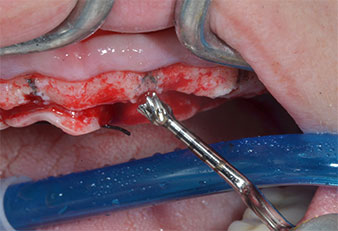

Un insert piézoélectrique diamanté de forme effilée (Piezomed I1) a été utilisé pour marquer les positions implantaires et effectuer la préparation pilote (Fig. 3). On a pris soin de travailler selon un mouvement ascendant et descendant, à puissance réduite, irrigation complète et basse pression (moins de 300g). Ensuite, un insert pilote (Piezomed I2A/I2P) a été utilisé pour l’agrandissement initial de 2mm du diamètre des sites implantaires (Fig. 4), suivi d’un insert de 3mm (Fig. 5).

En cas de densité osseuse élevée, il convient d’utiliser toute la gamme d’inserts, y compris les inserts intermédiaires Piezomed Z25P et Z35P afin d’élargir

les ostéotomies avant l’étape d'agrandissement suivante.

Ces inserts sont également indiqués pour les préparations à proximité de la membrane sinusienne dans le cadre

de procédures d’élévation par voie interne ou lorsque

la hauteur osseuse résiduelle est inférieure à 4mm.

Dans le cas présent, les inserts Z25P et Z35P n’ont pas été utilisés car l’os postérieur était relativement mou

et l’intervention sur celui-ci a été aisée avec le I3A/I3P.